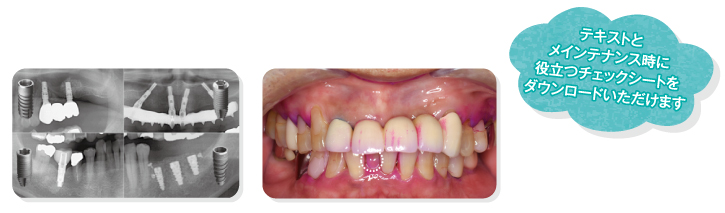

配信期間:2022年7月14日(木)~7月21日(木)> ※期間中は何度でもご覧いただけます。 ※配信期間終了後に見逃し配信を予定しております。 見逃し配信期間については本配信後にご案内いたします。 講演ポイント ●インプラントメインテンナスに必要な基礎知識 ●インプラントメインテナンスの実際を動画で説明 ●明日からの臨床に活かせるチェックシート配布 チャプター(講演時間:約100分) 1)歯科衛生士に知ってほしいインプラントの基礎知識 2)歯科衛生士が知りたいインプラントメインテナンスのポイント 3)CASE 4)浅賀歯科医院での実際の取り組み

「普段はなんとなくインプラント治療後のケアをしている」「インプラント患者が来院した時どう対応していいのかがわからない…」 このようなお悩みありませんか?インプラントは今や日本で300万人以上の人が受けられている治療です。 今後もさらに患者数は増えていくでしょう。インプラント患者のメインテナンスに自信を持って臨めるように、 インプラントに関する基礎知識から実際のメインテナンスのチェック項目まで全てお話しします。 ご略歴 ◆2013年 日本大学歯学部卒業 ◆2014年 医療法人 寛友会 浅賀歯科医院に勤務・院長を務める